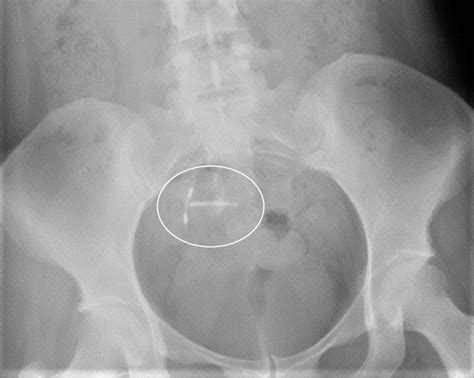

Phleboliths are small, calcified deposits that form within veins. They are typically composed of calcium and other minerals and can vary in size from a few millimeters to several centimeters. These deposits are often incidental findings during imaging studies, such as X-rays, CT scans, or MRIs. While phleboliths can occur in various parts of the body, their presence in the pelvis is particularly noteworthy due to the anatomical complexity of the region.

• X-Rays: Plain radiographs can sometimes detect phleboliths, especially if they are large enough. However, X-rays are less sensitive compared to other imaging modalities.